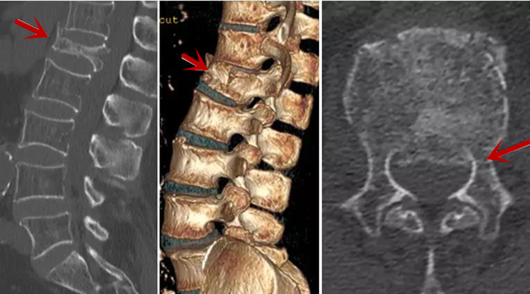

利器二:CT

CT利用X射线对人体检查部位通过电脑切成若干层扫描,然后把每层的图像都能显示出来。CT相对于X光片具有更高的密度分辨力,可直接显示X线片无法显示的病变,观察腰椎有无微小的骨折、骨质有无破坏等骨质情况、以及腰椎间盘突出、腰椎神经根、椎管、椎间小关节的情况等。同时还可以通过后处理,重建腰椎矢状位或冠状位图像,形成腰椎的3D图像,更直观地观察病变部位,对腰椎手术风险具有提示作用,对手术方式的选择具有指导意义,但是对神经、脊髓损伤程度的显示不如MRI,软组织的分辨率仍有一定限制,对椎管内病变显示欠佳,且有一定的辐射。

从左向右依次为CT矢状位重建图像、三维重建图像、轴位扫描图像,箭头提示腰1椎体爆裂性骨折